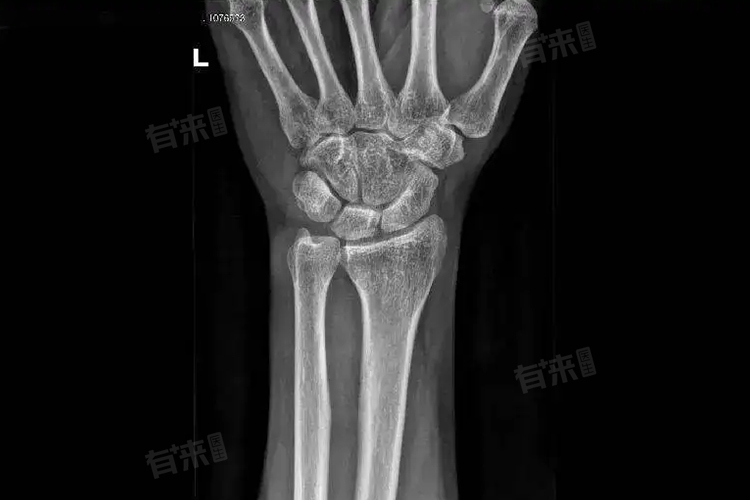

- R系列骨龄主要侧重于观察手腕部桡骨的骨骺发育情况,桡骨在儿童骨骼生长过程中具有代表性,其骨骺的出现、生长、闭合遵循一定的时间规律。通过对桡骨骨骺在X光片上的形态、大小、骨化中心的数量及融合程度等特征进行详细分析,依据标准的发育图谱或数据来确定R系列骨龄。例如在正常生长发育的儿童中,特定年龄阶段桡骨骨骺会呈现出相应的特征,医生借此对比判断儿童的骨龄是否与实际年龄相符,若桡骨骨骺发育超前或滞后,可能提示生长发育异常,如性早熟或生长激素缺乏等疾病可能导致桡骨骨龄异常变化。

- C系列骨龄则着重关注腕骨的发育状况,腕部的多块腕骨在儿童成长过程中也有着有序的发育进程。通过对腕骨整体的骨化程度、各腕骨之间的比例关系以及与年龄相关的特征性变化进行评估确定C系列骨龄。例如在幼儿时期,腕骨的骨化中心逐渐出现,随着年龄增长不断发育成熟,不同年龄阶段腕骨在X光片上呈现出不同的影像特征,医生依据这些特征来判断C系列骨级别的高低,从而辅助诊断儿童生长发育问题。

在进行R系列和C系列骨龄检测时,必须选择专业的医疗机构和有经验的医生进行操作,确保X光片拍摄质量清晰、准确,能清晰显示骨骼细节,以便精确评估骨龄。骨龄检测结果只是一个参考指标,不能仅凭此确诊疾病或判断儿童未来身高的绝对数值,要结合儿童的家族遗传史、临床症状、营养状况、内分泌检查等多方面综合分析。